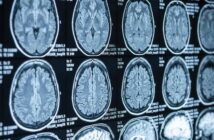

California Assembly Bill 460 modernizes contrast supervision by allowing remote radiologists, but with a critical catch: a licensed practitioner must still be physically on-site. This creates new operational and financial challenges. This definitive checklist covers the technology, documentation, and staffing requirements imaging centers must meet before the January 1, 2026, effective date to avoid severe penalties like False Claims Act liability and Medicare de-participation.